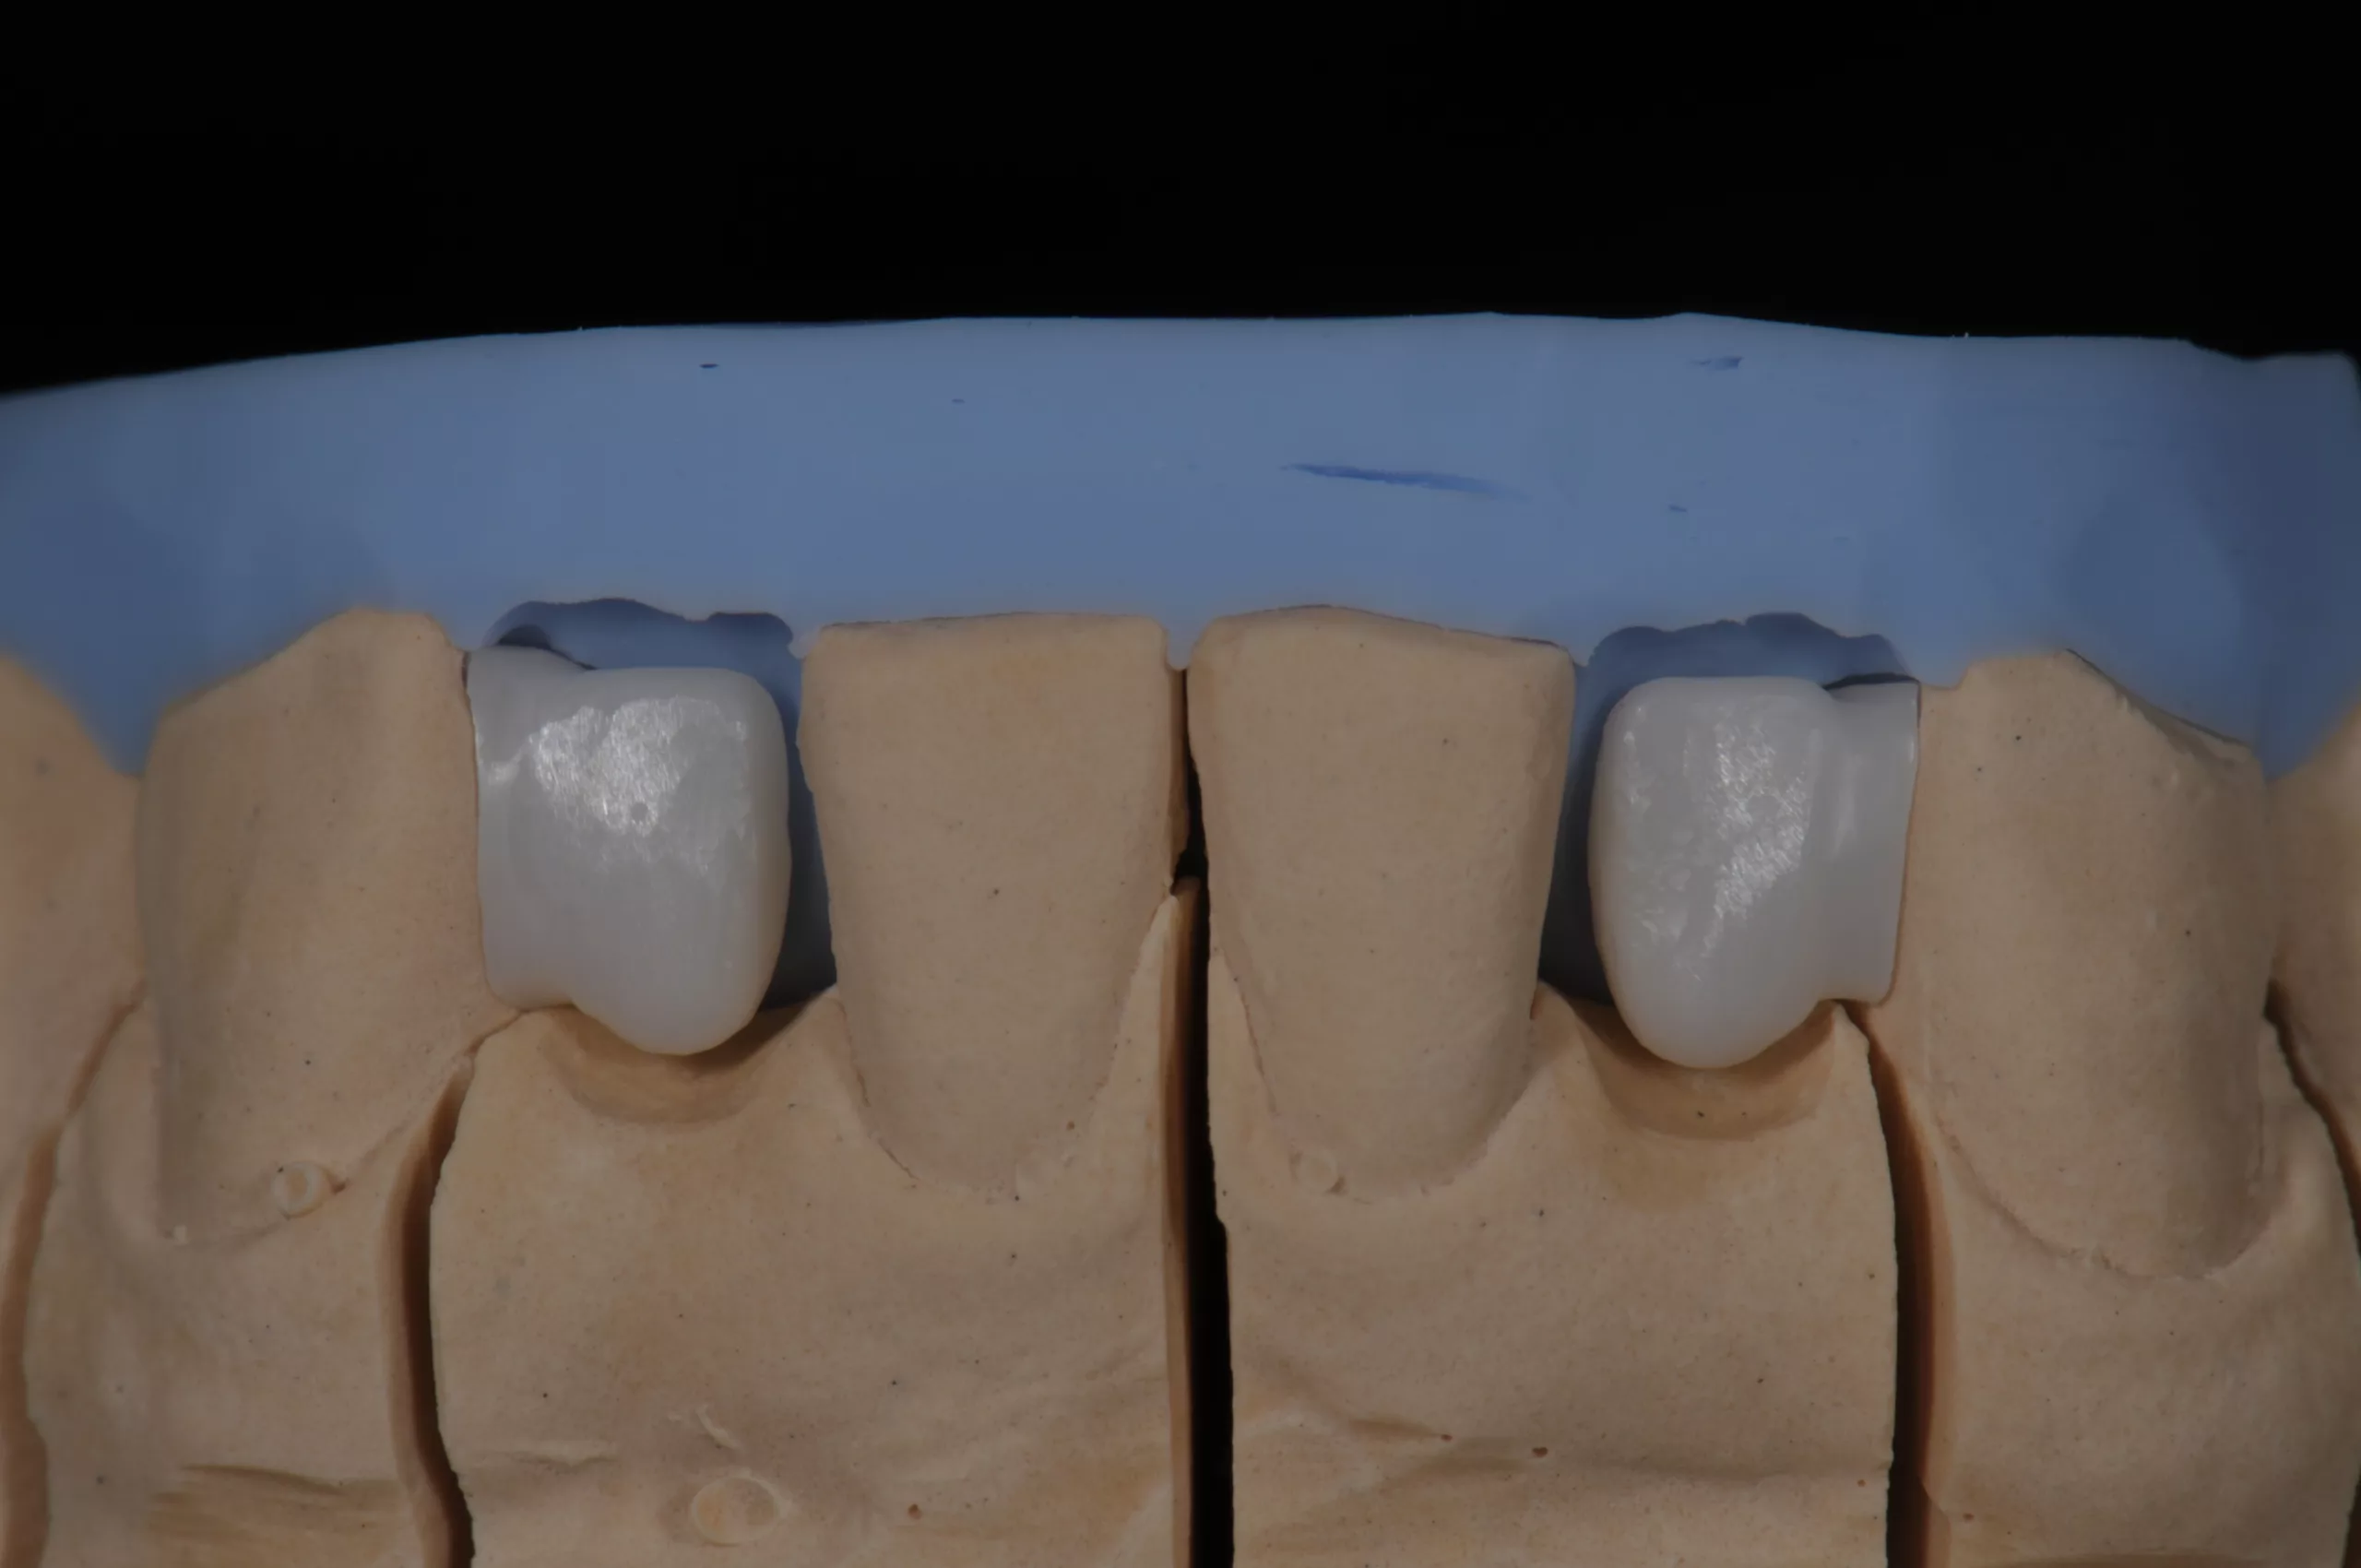

Laut aktueller Studienlage sind Gerüste aus Zirkoniumoxidkeramik als Material der Wahl zu empfehlen (Abb. 1) [1-3].

Im zahntechnischen Labor erfolgt die Herstellung des Zirkoniumdioxid-Gerüsts. Ein zuvor angefertigter Silikonschlüssel des Wax-Ups hilft dabei, die Ausdehnung des Gerüsts für eine optimale Unterstützung der Verblendkeramik festzulegen (Abb. 8). Der Verbinder sollte für die gesinterte Zirkoniumoxidkeramik einen Querschnitt von 7-9 mm2 nicht unterschreiten [10]. Nach Fertigstellung der Brücke (Abb. 9) erfolgt die intraorale Anprobe. Es werden Form, Farbe, Approximalkontakt und die Passung überprüft. Die Okklusions- und Artikulationskontakte können in diesem Stadium nicht am Patienten überprüft werden. Erst nach adhäsiver Befestigung können diese kontrolliert und ggf. durch Einschleifen feinjustiert werden.